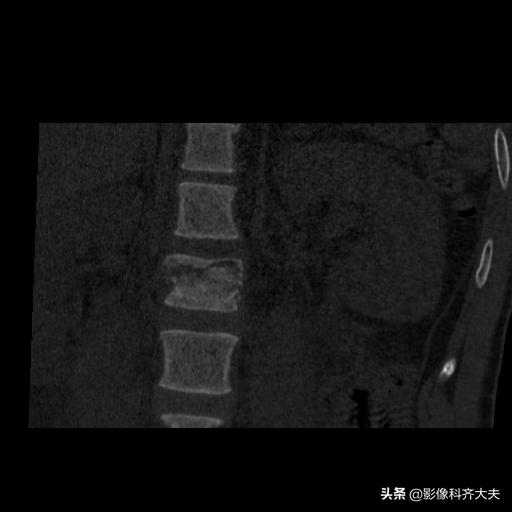

CT检查:

可见骨折椎体内出现横行、纵行、斜行、丫形等形态的骨折线

严重椎体骨折可出现“崩裂”状,表现为多数长短不等骨折线,酷似用力打碎的石板,使椎体分裂成大小不等骨块

椎体后缘骨折,可见游离在椎管内的骨折块大小、形态及位置

当附件骨折X线片显示不清时,CT检查可明确诊断

腰二横突骨折

VR重建

冠状面重建

矢状面重建